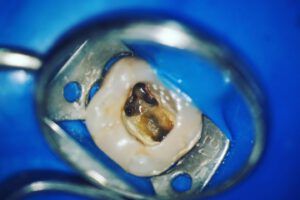

Leczenie kanałowe (endodontyczne) polega na usunięciu zainfekowanej lub martwej miazgi z wnętrza zęba, oczyszczeniu wszystkich kanałów korzeniowych i ich szczelnym wypełnieniu. Miazga jest tkanką odpowiedzialną za odżywianie i unerwienie zęba. Kiedy zostanie zaatakowana przez bakterie, powoduje silny ból, obrzęk i stany zapalne.

- Otwarcie komory i usunięcie miazgi – oczyszczenie komory i kanałów z chorej tkanki.

- Opracowanie kanałów – przy użyciu pilników ręcznych lub maszynowych, z obfitym płukaniem środkami odkażającymi.

- Dezynfekcja – płukanie kanałów specjalnymi środkami (np. podchlorynem sodu), czasem z użyciem lasera.